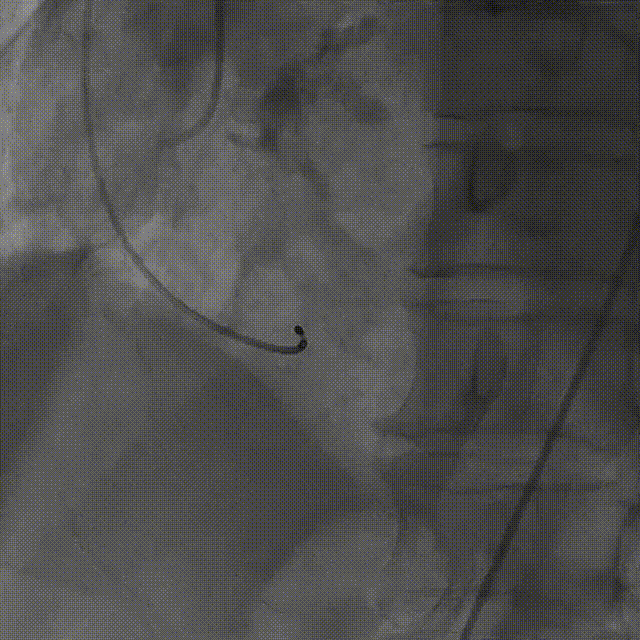

导丝顺利跨瓣

23mm球囊预扩无腰征,微量漏